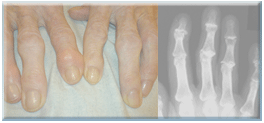

손가락관절염의 원인은 여러 가지이지만 주로 퇴행성 관절염과 류마티스성 관절염이 주를 이룹니다.손가락 관절을 보호하고 있는 연골이 닳아서 뼈와 뼈가 부딪히게 되면 골극(osteophyte)이라고 하는 여분의 뼈가 정상뼈 밖으로 자라나게 되며 이로 인해 통증이 유발됩니다.

진단

손가락 관절에 통증, 부종, 열감이 있으며 단순방사선촬영상 관절 간격이 좁아져 있습니다.필요에 따라 혈액검사를 통해 류마티스인자를 확인하기도 합니다.